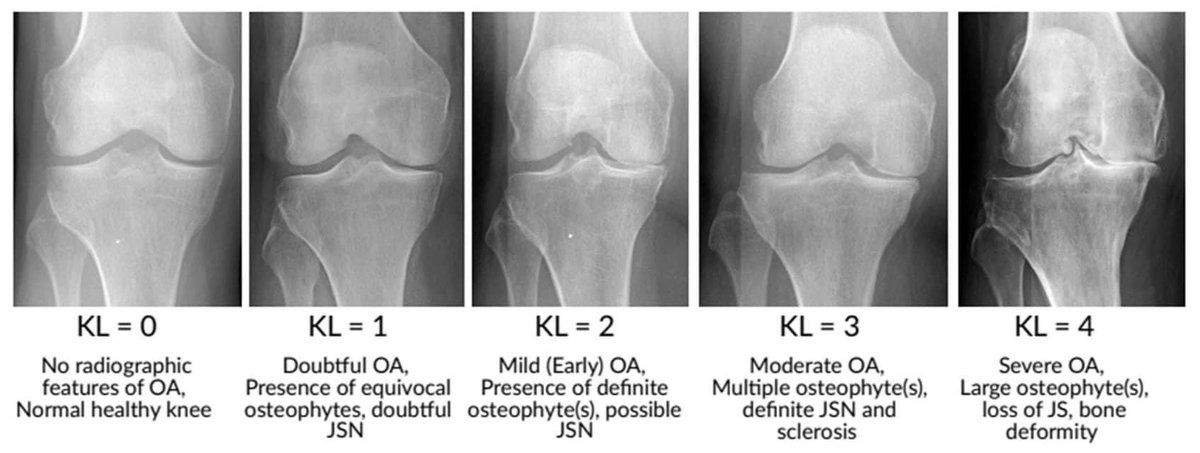

Radiografías convencionales

- Son la prueba de imagen estándar inicial.

- Permiten evaluar el estrechamiento del espacio articular, osteofitos, esclerosis subcondral y deformidades óseas que son típicas de la artrosis. elsevier.es

- El grado de artrosis en las radiografías se clasifica frecuentemente mediante la escala de Kellgren y Lawrence.

- No siempre existe una correlación directa entre hallazgos radiográficos y la intensidad del dolor o síntomas clínicos, por lo que deben interpretarse junto con la clínica del paciente. Madrid